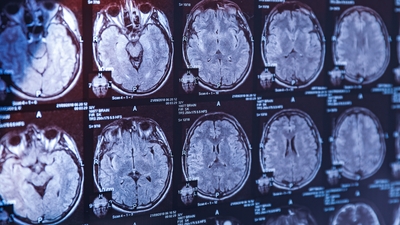

Araştırma sonucunda, şizofreni hastalarında NfL düzeylerinin sağlıklı bireylere göre daha erken yaşlarda ve daha hızlı arttığı gözlemlendi. Bu durum, şizofreni hastalarının beyinlerinin biyolojik olarak kronolojik yaşlarına göre daha yaşlı olduğunu ortaya koyuyor. Aynı araştırmada bipolar bozukluk yaşayan bireylerde ise benzer bir artış gözlenmedi. Bu da şizofreniyi diğer psikiyatrik bozukluklardan ayıran biyolojik bir farklılık olabileceğini gösteriyor. MRI taramaları da şizofreni hastalarında beynin yapısal olarak daha hızlı yaşlandığını destekliyor.